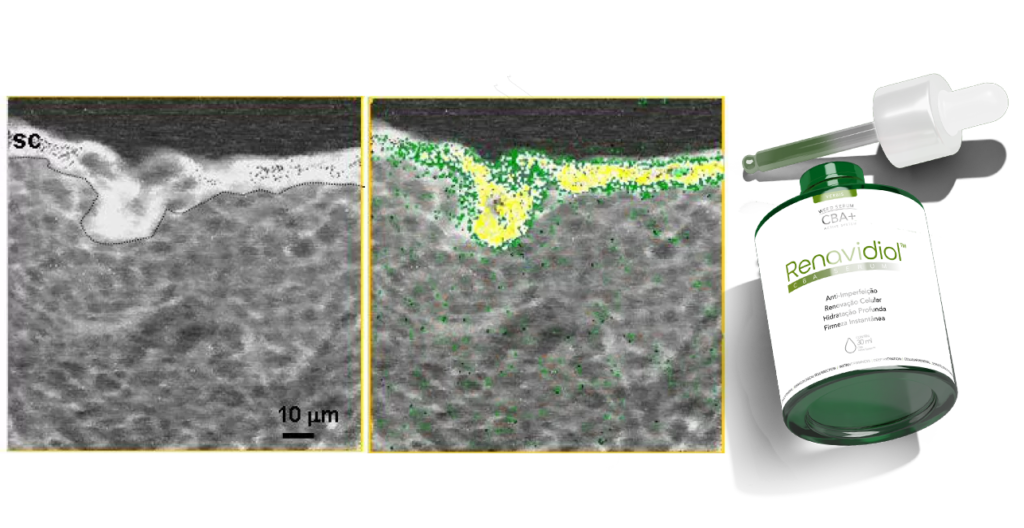

A tecnologia exclusiva do Renavidiol CBA Serum proporciona uma absorção rápida e eficaz diretamente pelas camadas da pele. Seus ativos, incluindo o poderoso CBA Active System™, penetram profundamente na pele, garantindo uma absorção de até 97%. Essa fórmula avançada atua diretamente onde sua pele mais precisa, proporcionando resultados visíveis em pouquíssimo tempo.

A fórmula do Canabinoid Active System™ contém uma exclusiva tecnologia premium e importada para aumentar a absorção do organismo aliada aos componentes premium do produto proporcionam um toque aveludado deixando sua pele mais lisa e revitalizada com uma mega hidratação 3D e resultados visíveis 24horas após o uso.